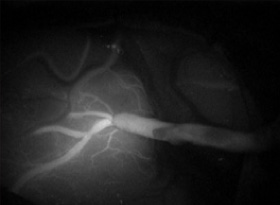

術中ICG蛍光造形1

術中ICG蛍光造形1

術中ICG蛍光造形2

術中ICG蛍光造形2

術中ICG蛍光造形3

術中ICG蛍光造形3